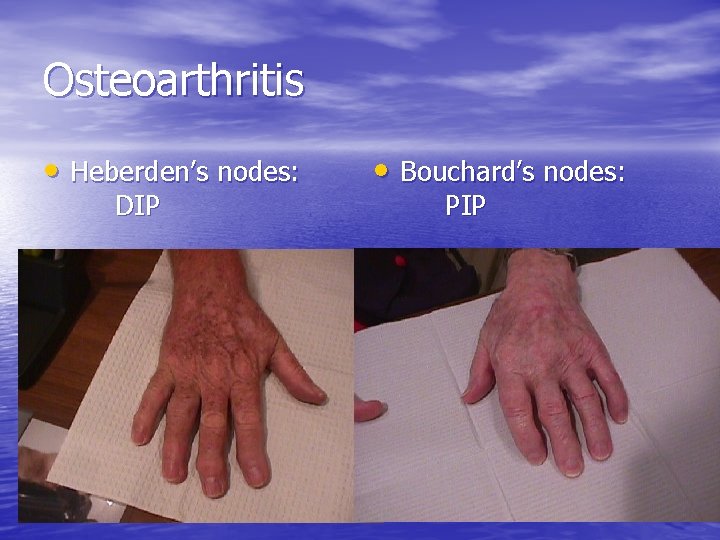

Osteoarthritis • Heberden’s nodes: DIP • Bouchard’s nodes: PIP